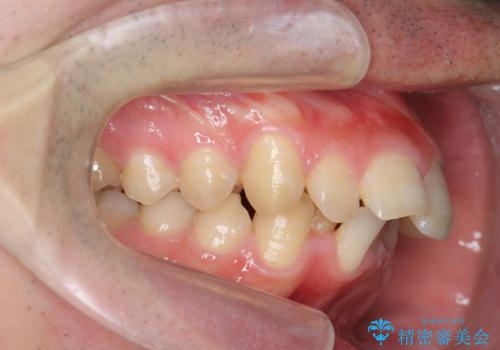

ガタつきの大きい前歯 インビザラインによるマウスピース矯正治療

- ガタつきの目立つ前歯の改善を求めて来院されました。

上顎前突、がたつきを改善すべく上顎臼歯の後方移動・ディスキングを行い歯並びの改善を計画します。

食事・歯ブラシ時以外の時間にしっかりとマウスピースを装着していただけたのでガタつきは大きく改善し良好な歯並びを得ることができました。